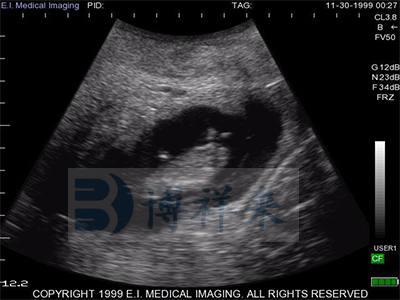

L7HD 高频线阵直肠探头(5-9MHZ可变) 高清分辨率

适用对象:牛马骆驼等大动物生殖检查、肌腱检查、新生犊牛肺部检查。

| 超声类型 | 数字超声 | 产科软件 | 各种动物妊娠期参数表格 |